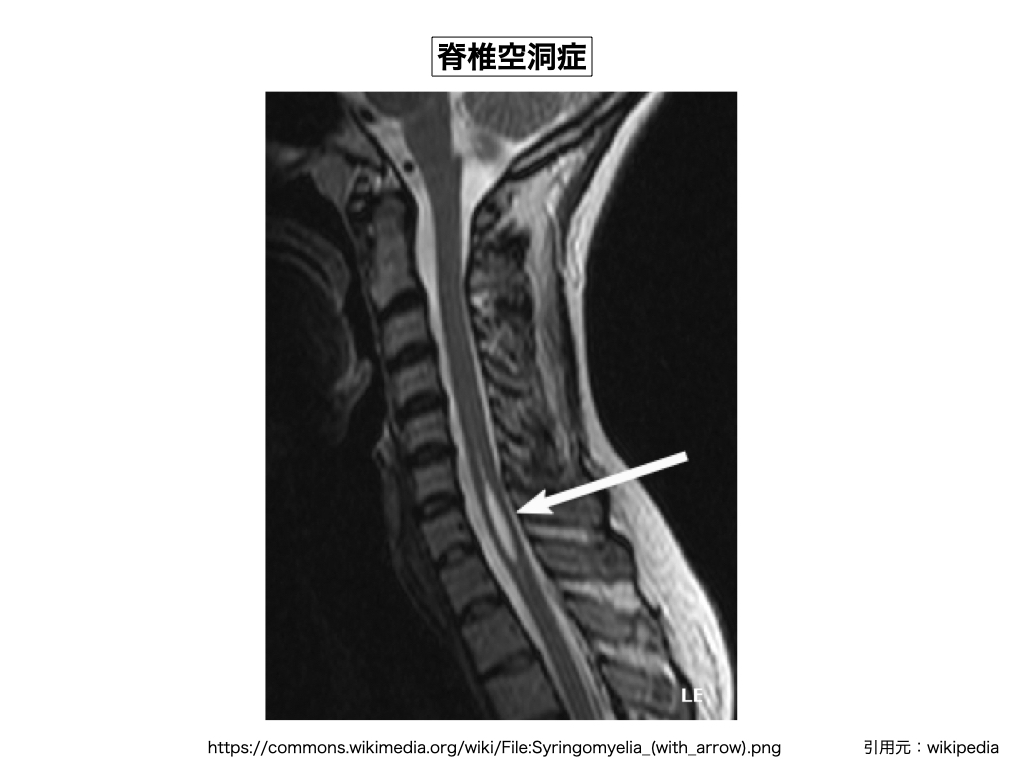

024) 脊髄空洞症

※ 脊髄空洞症とは脊髄の中に液体(脳脊髄液)の溜まった腔が出来た状態を指す(空間空洞が出来ている訳では無い)。症状としては脊髄内に形成された空洞の大きさに応じ、様々な程度の脊椎症状(四肢の運動麻痺、知覚障害、膀胱障害、直腸障害)として現れる。「キアリ奇形」などの先天性の脳障害でも発症するが、後天的にもクモ膜脳炎や、脊椎梗塞や、物理的な外傷によっても発症し、また正常圧水頭症(NPH)が原因(脳脊髄液の循環不全)で起こる場合がある。宇宙医療では脊椎空洞内に溜まった脳脊髄液を移動させたり、また処理する事が出来る為に大きな問題にはならないが、物質医学では「大後頭孔減圧術」や「空洞-クモ膜下腔シャント術」などの物理施行を用いて大掛かりな治療を施さなければならない。